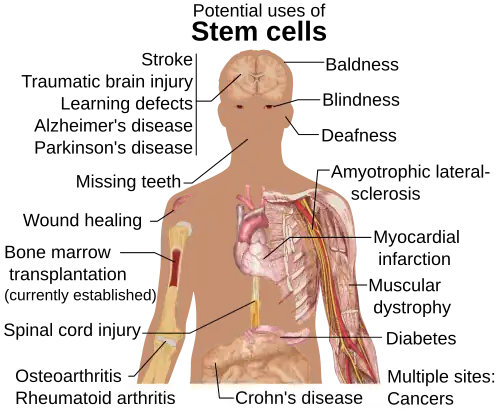

As células estaminais têm ainda a capacidade de se transformar, num processo também conhecido por diferenciação celular, em outros tecidos do corpo, como ossos, nervos, músculos e sangue. Devido a essa característica, as células estaminais são importantes, principalmente na aplicação terapêutica, sendo potencialmente úteis em terapias de combate a doenças cardiovasculares, neurodegenerativas, Diabetes mellitus tipo 1, acidentes vasculares cerebrais, doenças hematológicas, traumas na medula espinhal e nefropatias.[5]

O principal objetivo das pesquisas com células estaminais é usá-las para recuperar tecidos danificados por essas doenças e traumas.[6]

A terapia regenerativa com células-tronco encontrou uso na medicina veterinária.[8] Em 2011, no Zoológico de Brasília (Brasil), uma fêmea de lobo-guará, vítima de atropelamento, recebeu tratamento com células-tronco.[9] Este foi o primeiro registro do uso de células-tronco para curar lesões num animal selvagem.[8]

Assim, conforme sua grande capacidade de replicação, os estudos em células estaminais são de grande interesse para aplicações médicas; como dito anteriormente, é possível utilizá-las para tratamento de doenças humanas, bem como reparações de tecidos danificados.[10]